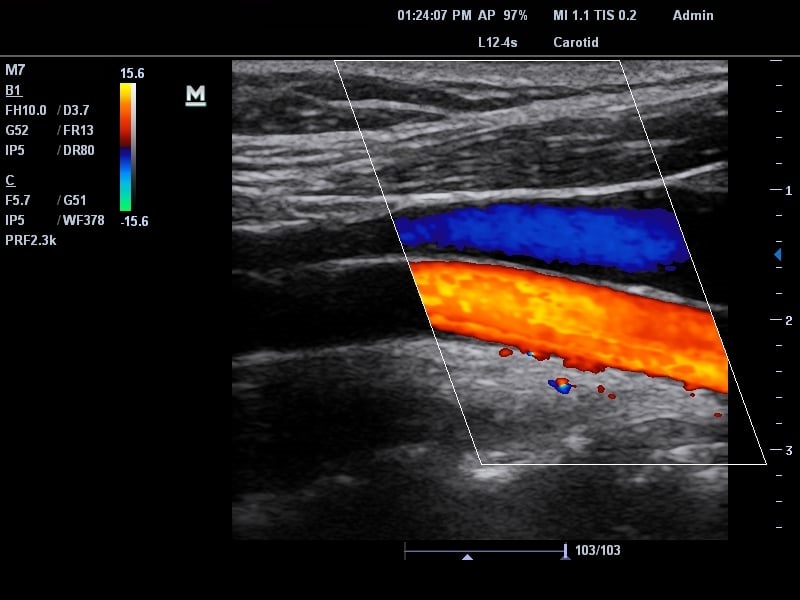

Siêu âm là kỹ thuật ứng dụng sóng âm thanh để tạo ra hình ảnh chi tiết về cấu trúc bên trong cơ thể. Các ứng dụng của phương pháp siêu âm rất rộng rãi, từ thăm khám thai đến chẩn đoán, phát hiện nhiều bệnh khác nhau, trong đó bao gồm cả siêu âm mạch máu chi dưới để chẩn đoán các tình trạng gây ảnh hưởng đến động mạch và tĩnh mạch của chi dưới.

Kỹ thuật siêu âm mạch máu chi dưới cung cấp những thông tin quan trọng liên quan đến mạch máu cũng như phát hiện các tổn thương (nếu có), đặc biệt là khi tích hợp siêu âm màu càng cho độ chính xác cao hơn. Hơn nữa, kỹ thuật siêu âm còn có ưu điểm là rất nhanh chóng, chỉ mất 20 đến 30 phút để hoàn thành việc kiểm tra. Bệnh nhân cũng không cảm giác bị đau hay khó chịu trong quá trình siêu âm nói chung, siêu âm mạch máu chi dưới nói riêng.

Các tĩnh mạch nông bao gồm tĩnh mạch hiển lớn và tĩnh mạch hiển bé. Kỹ thuật sử dụng sẽ có siêu âm B - mode để đánh giá hình thái trên suốt đường đi của tĩnh mạch. Ngoài ra còn tiến hành siêu âm doppler màu kết hợp doppler xung rồi đánh giá phổ doppler thu được để đánh giá chức năng van trong tĩnh mạch.